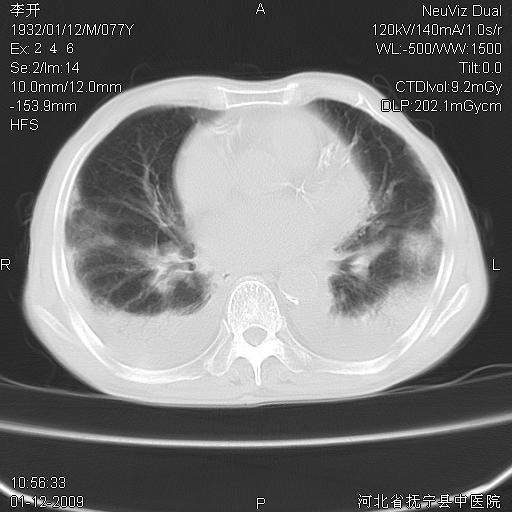

以下是引用黑白光影在2009-1-19 16:49:00的发言:[br]心衰肺水肿;心包、胸腔积液;冠脉钙化;肺部感染。